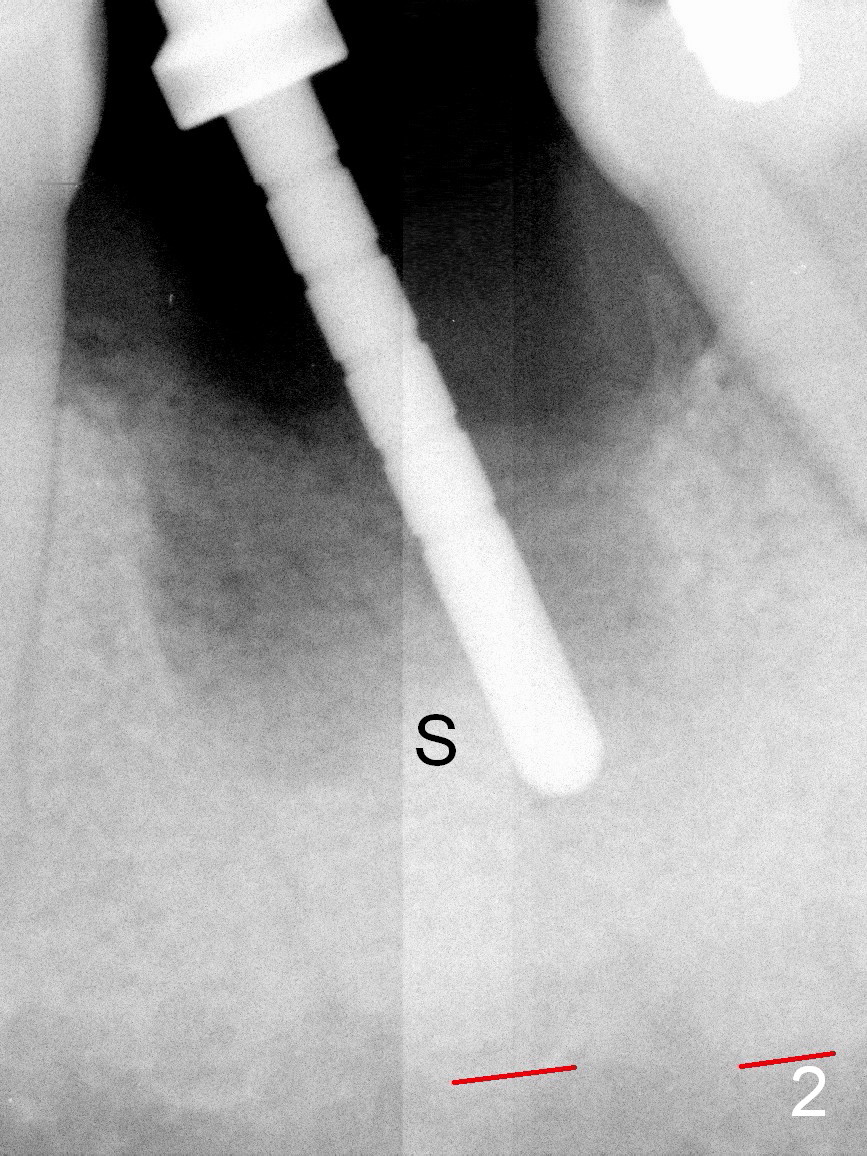

A 37-year-old lady (MP) presents to clinic with chief complaint of bad smell from lower right crown (Fig.1: #19; red dashed line: superior border of the Inferior Alveolar Canal). One of the most prominent pathologies is fracture of the distal root (<). After extraction, the socket is treated with 2% Xylocaine/1:50,000 Epinephrine. The coronal distobuccal plate is defective. Osteotomy is initiated as lingual as possible. The 1st intraop PA shows that the osteotomy is shallow and distal to the almost non-existent septum (Fig.2 S). The osteotomy is intended to move more mesially, but the result is not obvious when 4.5x14 mm drill is in place (Fig.3 D). The depth of the osteotomy is increased by 3 mm; a 5x17 mm tap is stable (Fig.4 T). A 5x12 mm implant (Fig.5 I) is placed until it cannot be turned. The implant is higher than the distal crest (^). In addition there is space apical to the implant (Fig.5*). After 5 mm drill is used, the implant is seated deeper with insertion torque < 35 Ncm (Fig.6). It suggests overprep. Anyway, an immediate provisional is fabricated after placement of an abutment (A). After reline, the provisional fits well. It has to be removed with forceps for occlusal adjustment. Finally the abutment/implant complex turns in the socket with fingers. The rotation/position of the complex is randomly adjusted. When the provisional is cemented, it does not seat completely, but is stable. If the implant osteointegrates, the provisional must play a role in stabilizing the implant. Bone graft is placed in the gap prior to cementation (Fig.6 *).